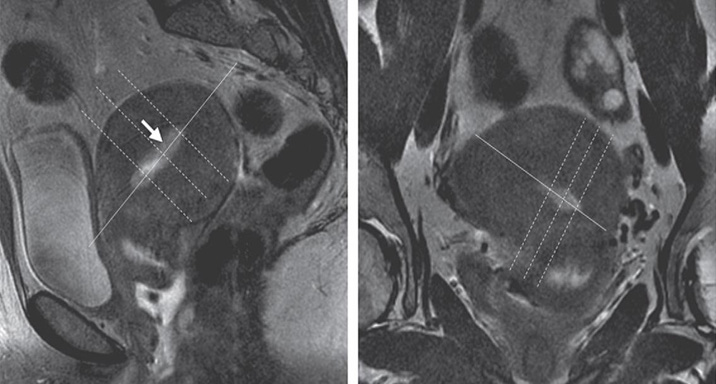

RadioGraphics 2014; 34:1082–1098 Figure 2. Obliques. Illustration shows a uterus that is ante¬riorly rotated in the sagittal plane (anteverted) and laterally tilted to the left in the coronal plane. The double oblique sequence is performed by an¬gling images anteriorly in the sagittal plane (green line) and laterally in the coronal plane (blue line), which creates true oblique images along the true axis of the uterus (orange line). A = anterior, P = posterior.

Figure 2. Obliques. Illustration shows a uterus that is ante¬riorly rotated in the sagittal plane (anteverted) and laterally tilted to the left in the coronal plane. The double oblique sequence is performed by an¬gling images anteriorly in the sagittal plane (green line) and laterally in the coronal plane (blue line), which creates true oblique images along the true axis of the uterus (orange line). A = anterior, P = posterior.

AX OBLIQUE T2 TSE 3 mm 0.5 mm N 200-240 mm/ Fit to Patient. Uterus → rectum Use all planes to obtain true axial of the endometrial canal (see images below). Matrix 512 x 256-512. Freq A-P.